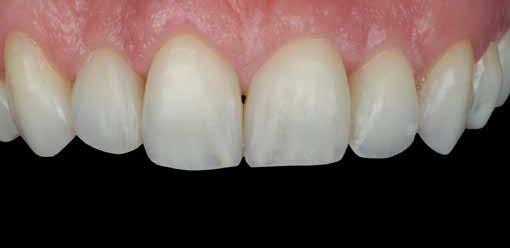

Egy 30 éves, negatív kórtörténettel rendelkező beteg azzal a kéréssel fordult hozzánk, hogy cseréljük ki az UR1 traumája után, 10 évvel korábban készült korábbi kompozit-helyreállítást.

A klinikai vizsgálat során az UR1 reagál a viabilitási tesztre, és az ugyanazon a napon készült röntgenfelvételen nem mutat periapikális elváltozásokat (1. ábra).

Az UR1 elszíneződött, és palatálisabb helyzetben van, mint az ellenoldali központi UL1 (2. ábra)

Az esztétikai elemzés a gingivális zenit aszimmetriáját mutatja az UR1 és az UL1 között. Parodontális szonda segítségével, plexusérzéstelenítés után, az IA

típusú funkcionális hám megváltozott passzív erupcióját igazoljuk Coslet és mtsai. osztályozása szerint (3. ábra)

A lehető legkonzervatívabb helyreállító kezelés elvégzése érdekében a páciensnél, figyelembe véve a megtartott fogelem korát és vitalitását, a tervezés és a diagnosztikai felviaszolás után a közvetlen kompozit-helyreállítás elvégzése mellett döntünk.

A finírozási és polírozási eljárásokat úgy végezzük, hogy megpróbáljuk emulálni az UL1 átmenő vonalait (12–13. ábra)

A pácienst 21 nap (14–15. ábrák) és 12 hónap (16. ábra) után ismét ellenőrizzük, hogy értékeljük az esztétikai eredményt a forma és a szín tekintetében.